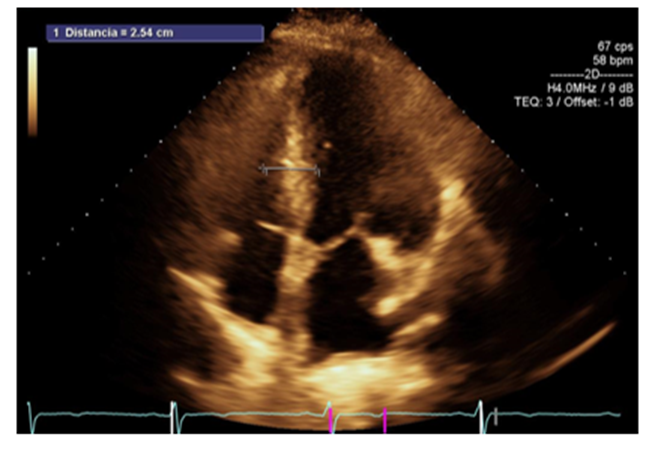

Figure 1: Apical 4-chamber axis showing asymmetric septal hypertrophy